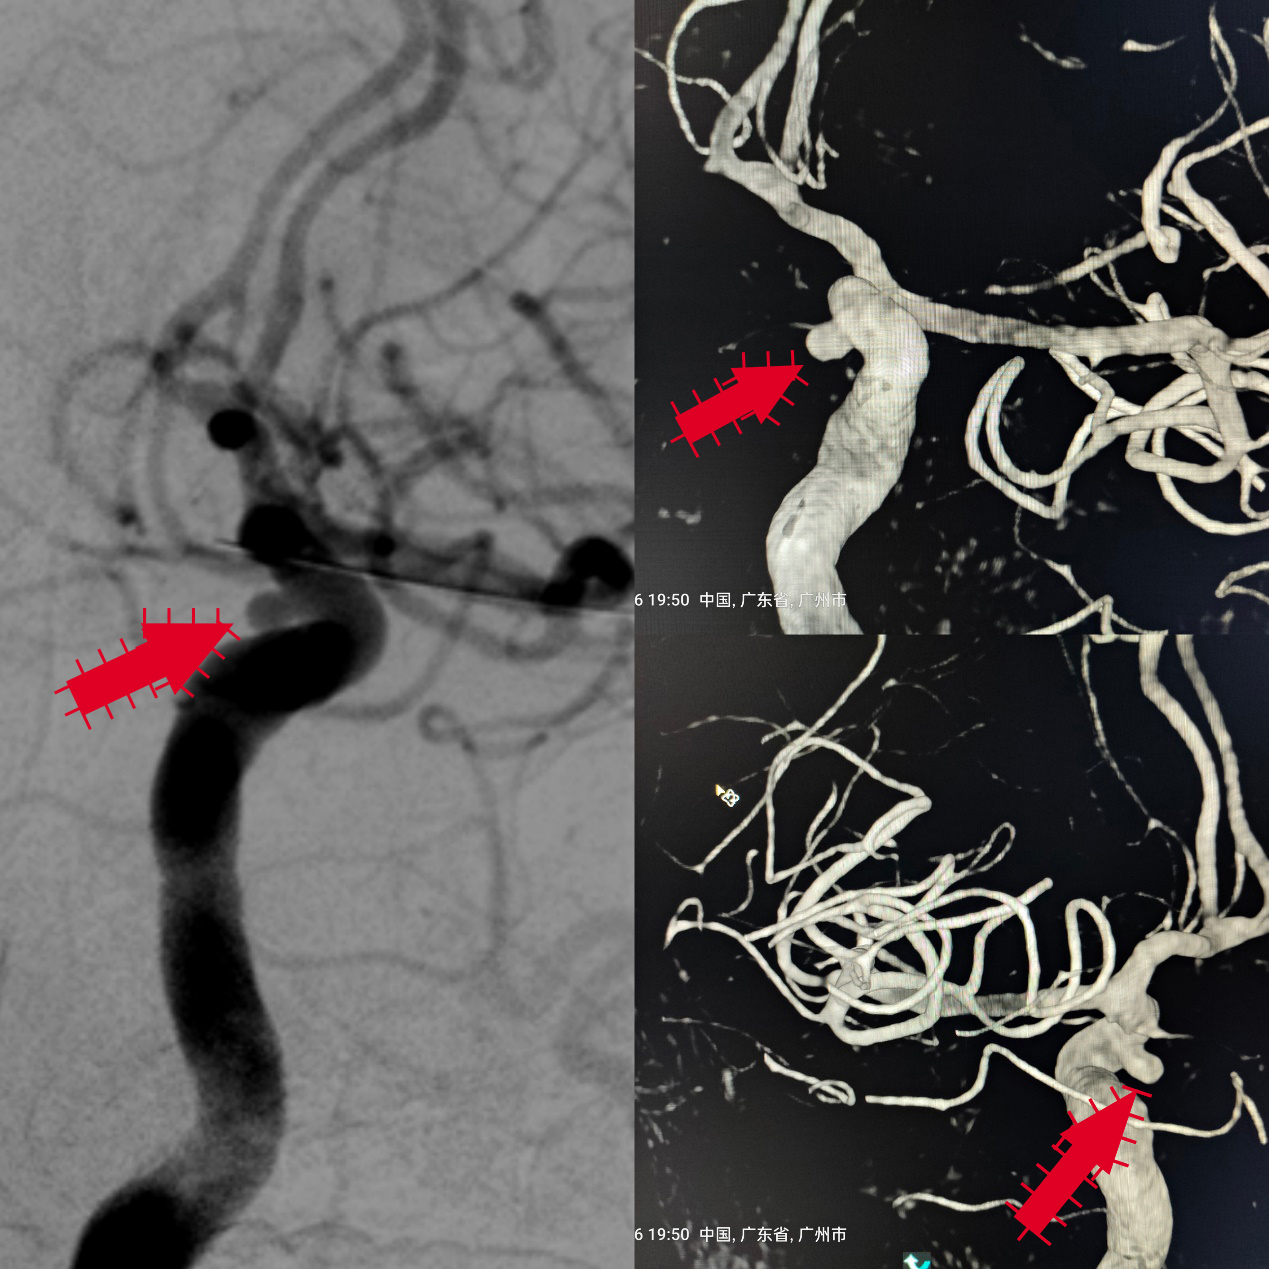

该患者是一名中年男性,因周围性面神经麻痹在我神经内科一区住院,住院期间完善头颅MRA提示可疑左侧颈内动脉眼动脉段动脉瘤(图1),脑血管造影及3D图像重建明确了左侧颈内动脉眼动脉段动脉瘤形态,位置及大小(图2)。

图2